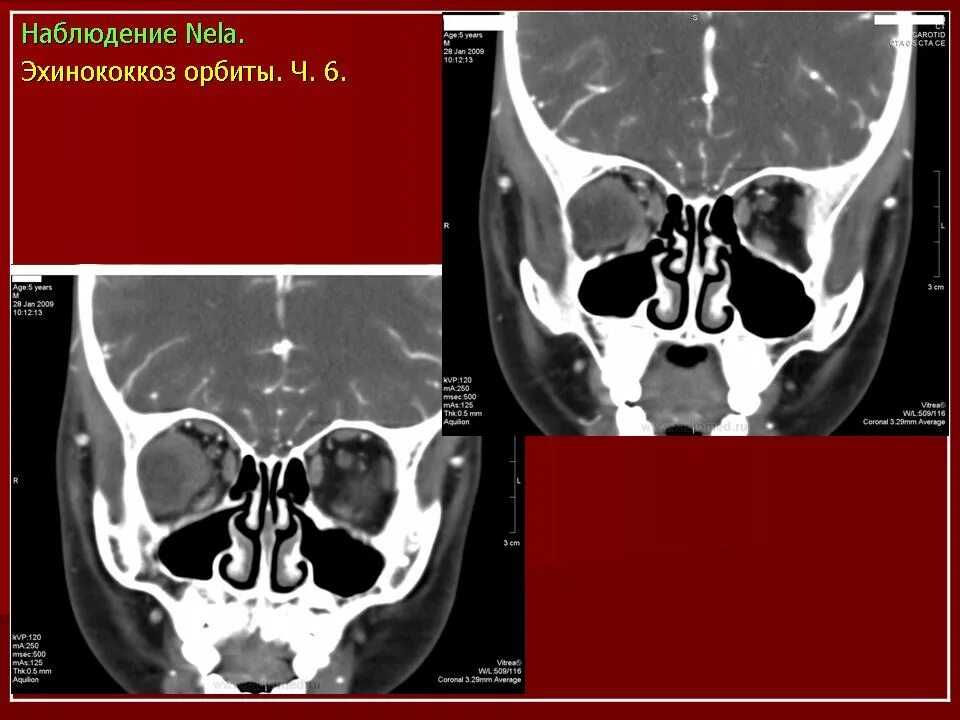

Данные кт